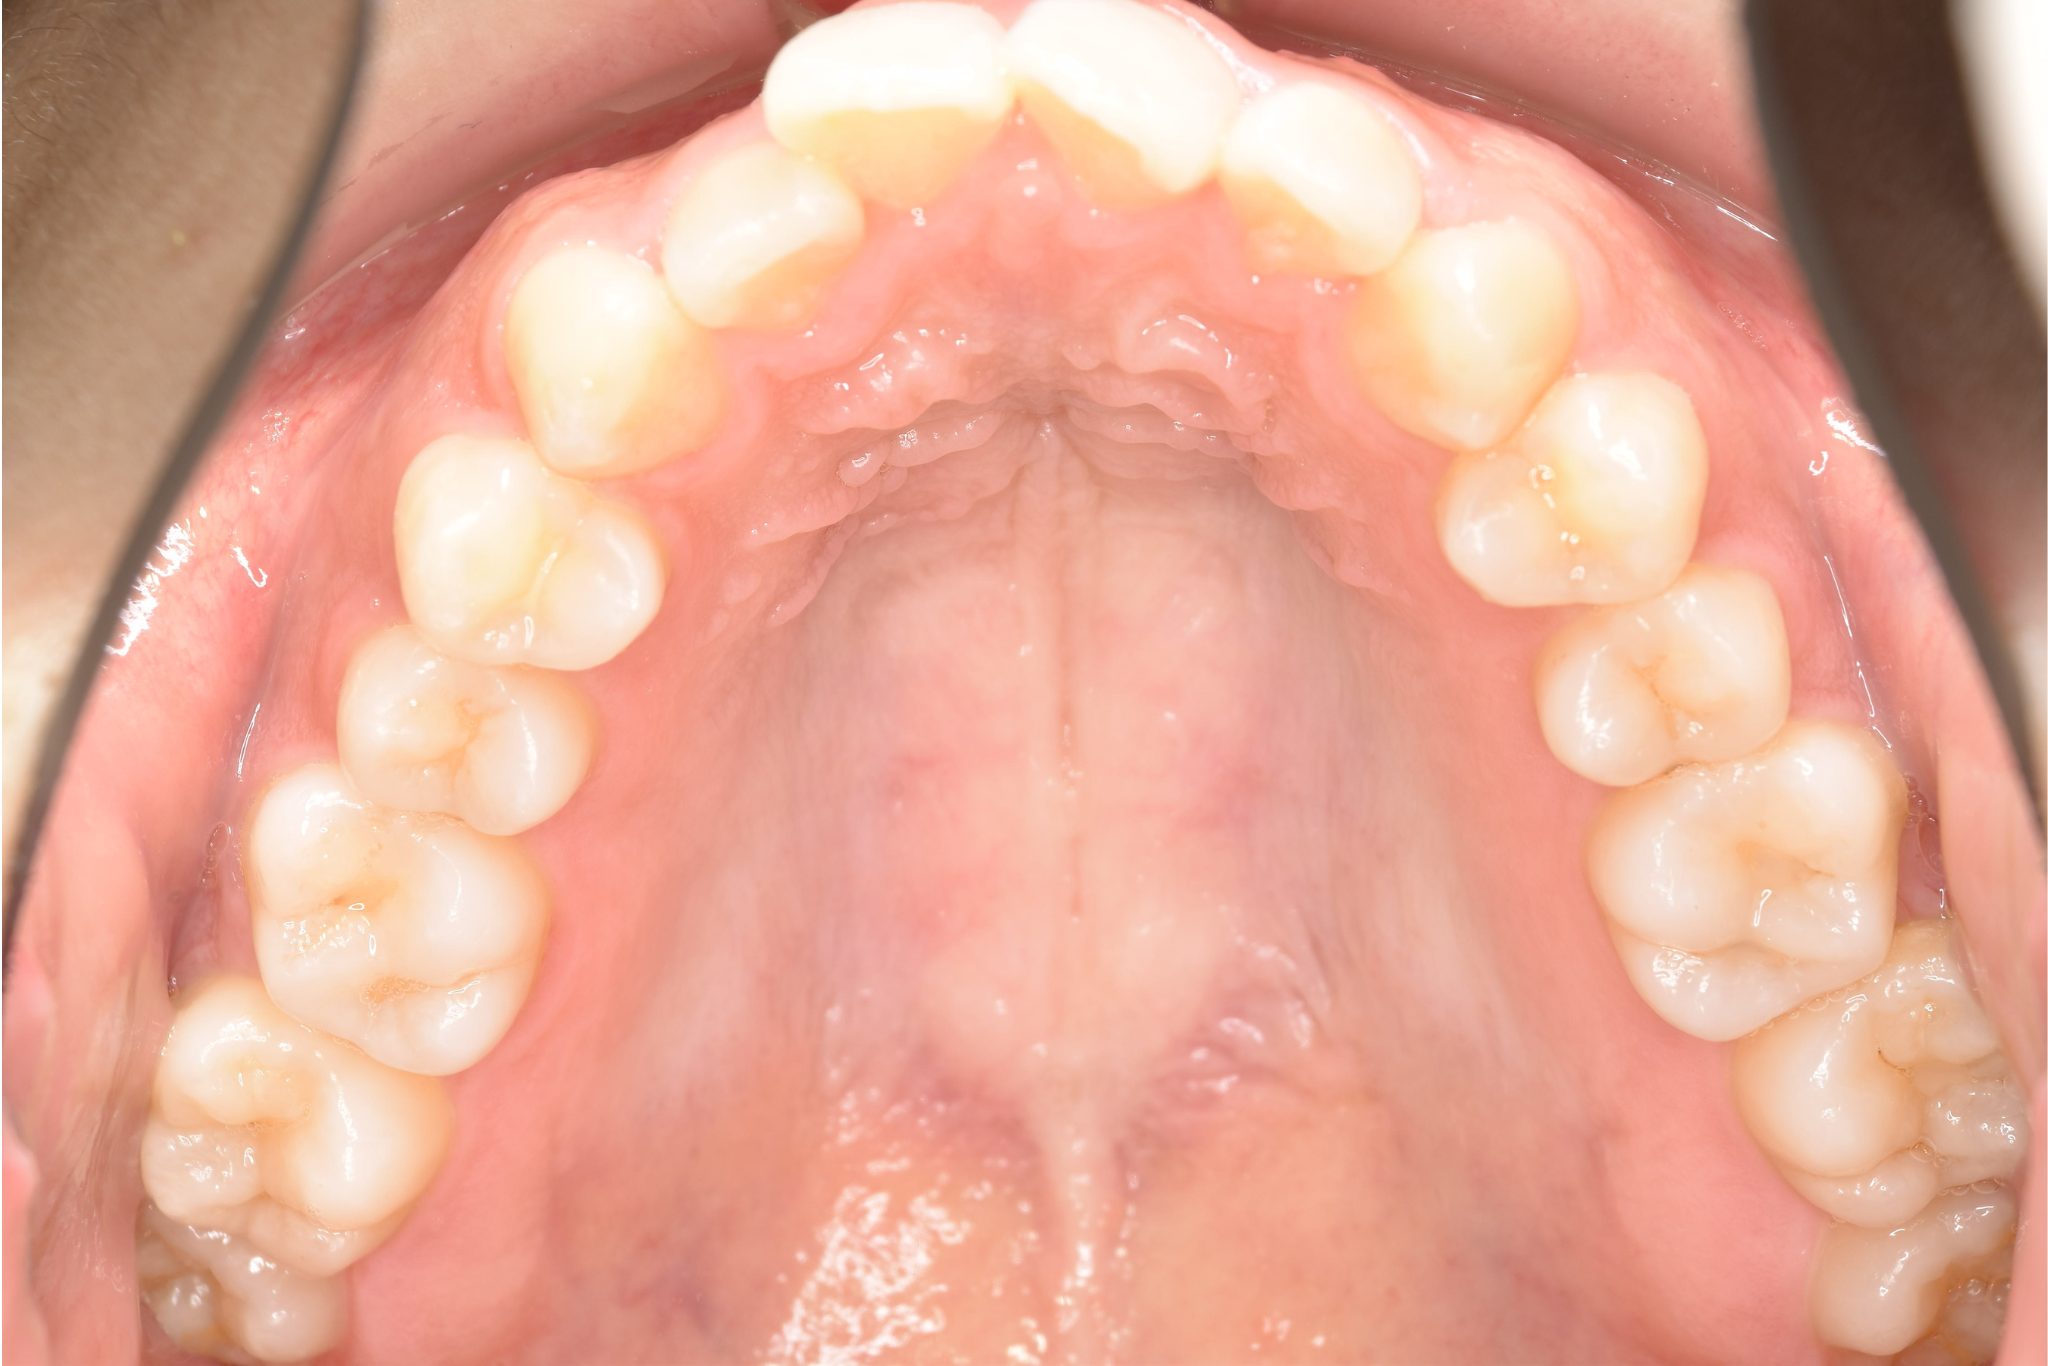

ビフォー

インビザライン矯正治療|症例_315